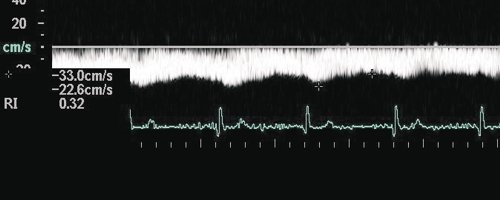

Среди всех видов аномальных кровотоков в воротной вене наиболее важным, с точки зрения кардиосовместимой допплерографии при дифференциальной диагностике первичных и вторичных печеночных болезней, является пульсирующий кровоток (рис. 7).

Рис. 7. Вариант пульсирующего кровотока в воротной вене.

Такая пульсация кровотока в воротной вене напрямую связана с деятельностью правого сердца через печеночные синусоиды. Она возникает при повышении давления в правом предсердии и при повышении центрального венозного давления (ЦВД). Поэтому пульсирующий допплеровский спектр кровотока "привязан" к комплексу QRS на ЭКГ. В этом случае минимальная скорость воротного потока соответствует систоле желудочков сердца. Он оценивается по так называемой шкале градаций пульсации потока в воротной вене. При нормальном давлении в правом предсердии, т.е. до 10 мм. рт. ст., отмечаются: 1-я и редко 2-я градации. При повышении давления в ПП градации увеличиваются. При наличии трикуспидальной недостаточности отмечаются 4-я или 5-я градации. Следует обратить внимание на отсутствие корреляции между степенью трикуспидальной недостаточности и шкалой пульсации в воротной вене. Феномену пульсирующего кровотока в воротной вене часто сопутствует спленомегалия. Оценка портальной гемодинамики в рамках кардиосовместимой допплерографии проводится при сопоставлении показателей кровотока в воротной вене с уровнем функционирования левого желудочка (УИ, СИ, УПС за 1 кардиоцикл). Пульсирующий кровоток в воротной вене требует анализа, аналогичного анализу артериального кровотока с учетом RI и PI в сочетании с оценкой функции правого предсердия и транстрикуспидального кровотока.